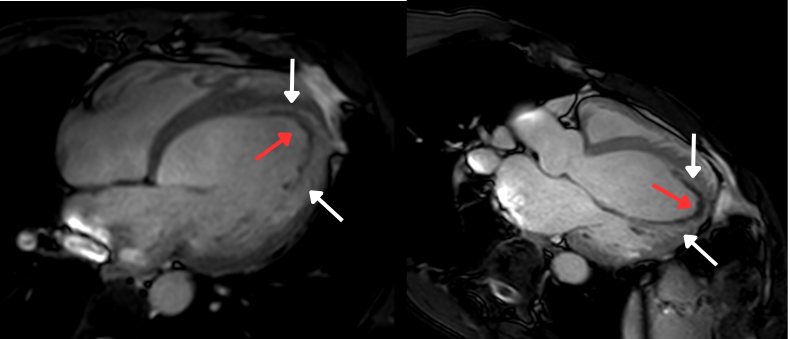

First-pass perfusion and Cine SSFP sequences. Large apical filling defect - white arrows. Apical mural thrombus - red arrows.